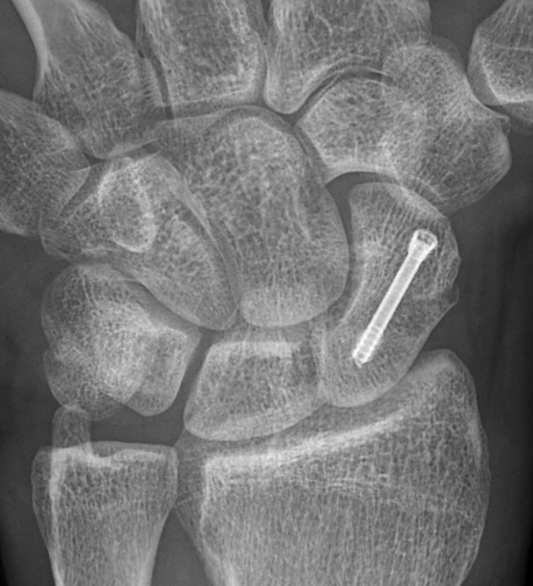

Percutaneous surgery for scaphoid fractures

For fractures of the waist of the scaphoid where the bone has not shown progression towards healing, a percutaneous operation can be done. For this operation a guide-wire is passed...